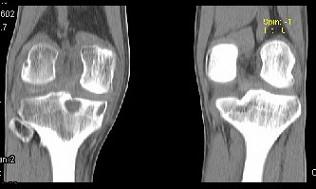

问题 男,38岁,膝关节肿痛,关节弯曲畸形,活动范围受限,胸片示两上肺有斑点状模糊影,请结合所提供的图像,选择最佳选项 ( )

选项 A、膝关节类风湿关节炎 B、膝关节痛风 C、化脓性骨关节炎 D、膝关节退行性变 E、膝关节结核

答案 E